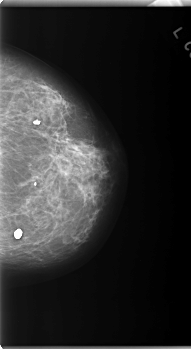

C_0171_1.RIGHT_CC

LEFT_CC LINES 5928 PIXELS_PER_LINE 3240 BITS_PER_PIXEL 12 RESOLUTION 50 NON_OVERLAY